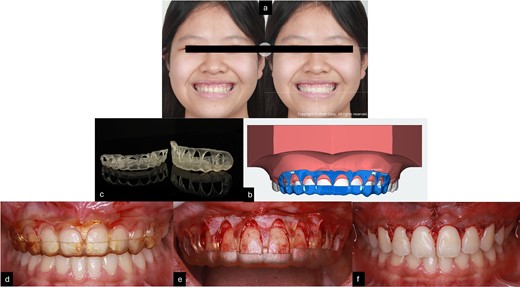

The crown-root ratio of the upper front teeth can be adjusted by removing enough bone while maintaining the biologic width. This involves two procedures: osteotomy, which entails removing enough bone while maintaining the biologic width, and osteoplasty, which involves curving the alveolar crests, creating lateral grooves, and thinning the bone border. To make the surgery simpler and more controlled, 2D smile design [8] on smile picture a 3D simulation, and an 3D guide design [9] were used to create a surgical guide for the gingivoplasty procedure. The treatment was performed by periodontist with laser for gingivectomy and handpiece for gingivoplasty (Fig. 4).

(a) Smile design before gingivoplasty treatment; (b) 3D printing gingivoplasty guide; (c) 3D guide design; (d,e) gingivoplasty treatment with guide; (f) post-treatment.